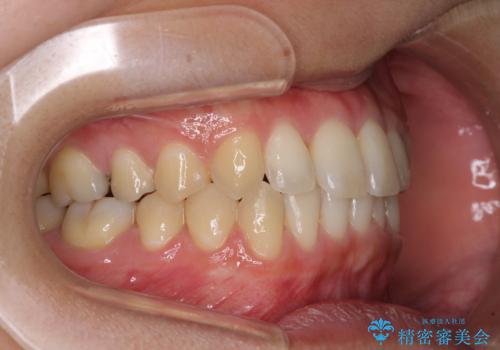

海外勤務中のインビザラインによる矯正治療

- 前歯のクロスバイトを気にして来院され患者様です。

定期的に日本には帰国するものの、日ごろは海外でお仕事をされているとのことで、インビザラインによる治療を希望されました。

トラブルが起こった時に対応ができない、来院を帰国のタイミングに合わせなければならないため治療が長期化するなど困難はありますが、ワイヤー矯正と比べると治療を進めやすいといったメリットがあるので、インビザラインにて矯正治療を行うこととしました。

治療期間が世界的な感染症の流行時期と重なったため、海外と日本での往来が困難となり、治療継続が懸念されました。

それでも、しっかりとマウスピースを装着してくださったので、大きなトラブルもなく治療を終えることができました。